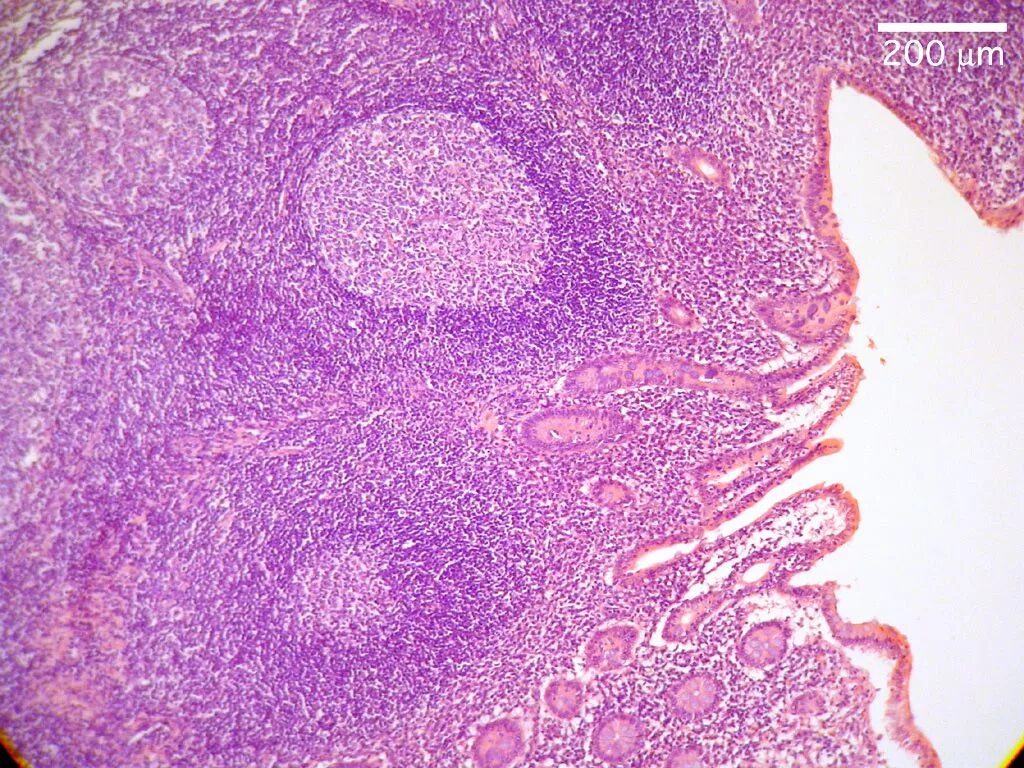

Гистология после